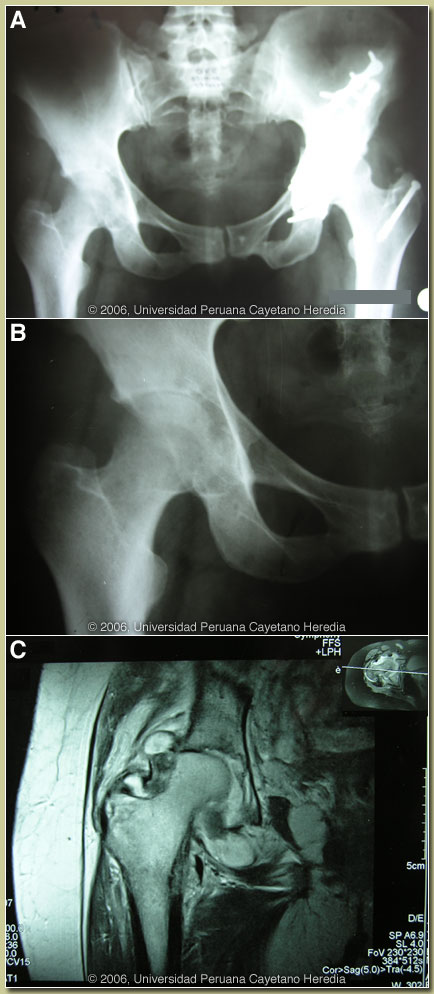

| Diagnosis: Mycobacterium tuberculosis infection of the right hip. |

The plain films of the hip [Image A] disclose the old fracture with prosthetic material on the left side. The close-up of the right hip [Image B] shows marked narrowing of the superior margin of the hip, erosive lesions on the medial-inferior surface of the femoral head, and marked irregularities on the surface of the acetabulum. Image C is a T2 weighted MRI that shows narrowing of the superior margin of the right hip, and disappearance of the cartilage in the remaining joint space. The medial and inferior part of the joint is widened and occupied by a white material consistent with fluid inside the joint. Irregularities and erosions on the acetabulum are also seen. These images (bone destruction with effusion) and clinical picture are consistent with chronic hip arthritis. In Peru, tuberculosisis is by far the most common diagnosis. Other considerations would be chronic pyogenic arthritis (no granulomas would be expected), brucellosis (negative serology for Brucella in this case and culture is still negative), and fungal arthritis (sporotrichosis and histoplasmosis occur in Peru but are a rare cause of chronic arthritis). Skeletal infection accounts for up to a third of cases of extrapulmonary tuberculosis with spinal tuberculosis (Pott?s disease) being the most common. Tuberculous arthritis occurs mostly in the weight-bearing joints, the hip and the knee, and is usually monoarticular. Most often other manifestations of TB are not present and infection is likely due to hematogenous seeding from a self-contained primary lung infection. Constitutional symptoms are present in the minority and progression of joint destruction and disability is usually indolent. Aspiration of joint fluid is usually unhelpful and synovial biopsy should be performed in suspected tuberculosis though acid-fast organisms are often not seen in tissue. Culture in our case is still pending but given the positive PPD, the caseating granulomas and all other cultures and stains being negative, we have begun the patient on four-drug tuberculosis therapy. Traditionally, because of poor drug penetration into bone, skeletal tuberculosis has been an indication for 12-18 months of therapy but a number of recent studies have suggested that standard-duration therapy may be adequate.